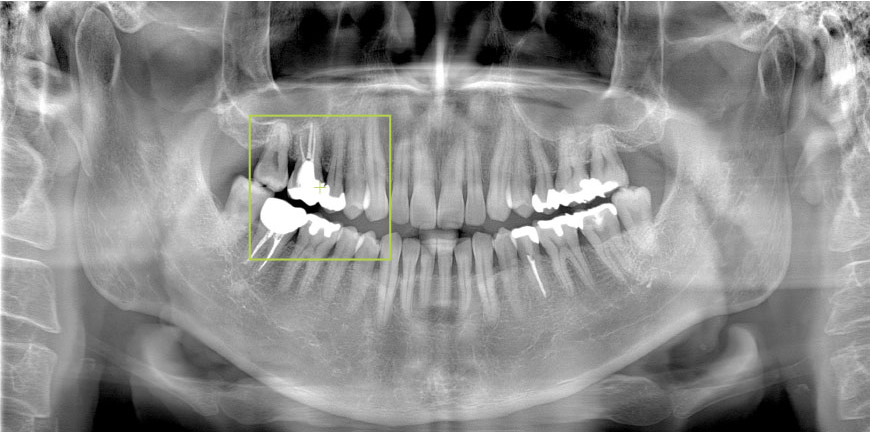

パノラマからCT撮影を自動位置づけ

パノラマ画像